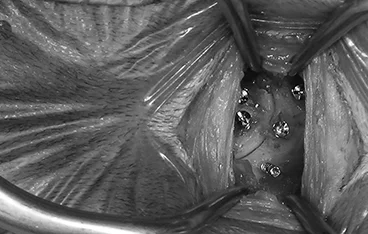

ventral slot, hemilaminectomy

• 흉요추 디스크